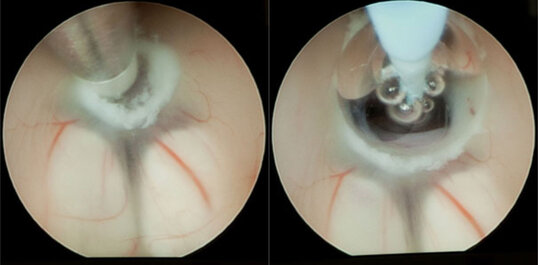

Kommt es zu einer Verlegung der Hirnwasserzirkulation, z. B. durch eine Verengung zwischen der dritten und vierten Hirnwasserkammer (Aquäduktstenose), kann ein sog. Verschlusshydrocephalus (Hydrocephalus occlusus) resultieren. Auch Tumoren innerhalb der Hirnwasserkammern können die Abflusswege verlegen und zu einem Verschlusshydrocephalus führen. Bei diesen Formen des Hydrocephalus kann durch eine ETV eine Verbindung zwischen dem III. Ventrikel und den äußeren Liquorräumen geschaffen werden. Hierbei wird über ein kleines Bohrloch im Schädelknochen ein Endoskop bis in den III. Ventrikel eingeführt und dessen Boden durch eine Perforation zu den äußeren Liquorräumen (basale Zisternen) gefenstert. Dadurch kann ein ungehinderter Liquorfluss unter Umgehung des Hindernisses ermöglicht werden.

Links: Darstellung der deutlich erweiterten Seitenventrikel. Rechts: Darstellung der Aquäduktstenose.